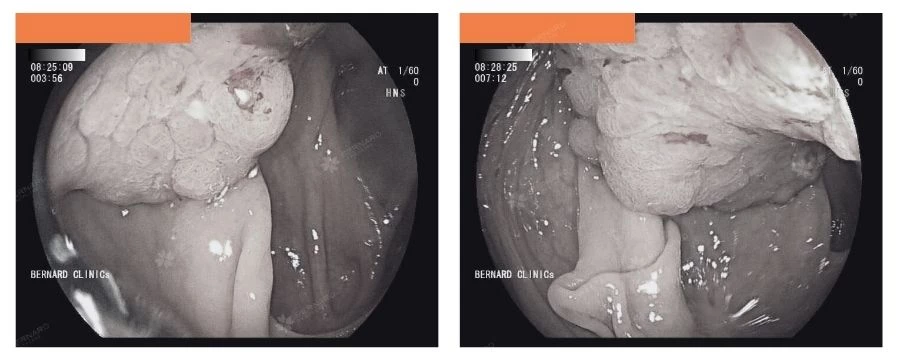

Cụ thể, khu vực góc gan – đại tràng phải phát hiện tổn thương dạng Lateral Spreading Tumor (LST) có kích thước lớn (khoảng 6x8cm), chiếm nửa chu vi lòng đại tràng, kèm theo vài túi thừa.

Theo quy trình chẩn đoán, tổn thương được bác sĩ thực hiện sinh thiết trong quá trình nội soi và gửi giải phẫu bệnh.